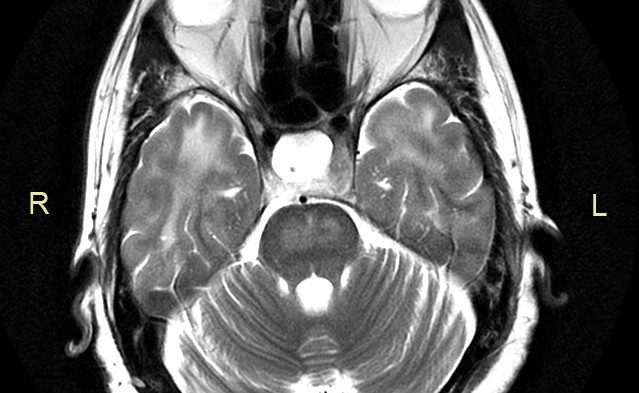

Extra Pontine Myelinolysis: a case report

The first case of extra pontine myelinolysis was described in 1987 and before that the concept of central pontine myelinolysis was being widely used. When extra...